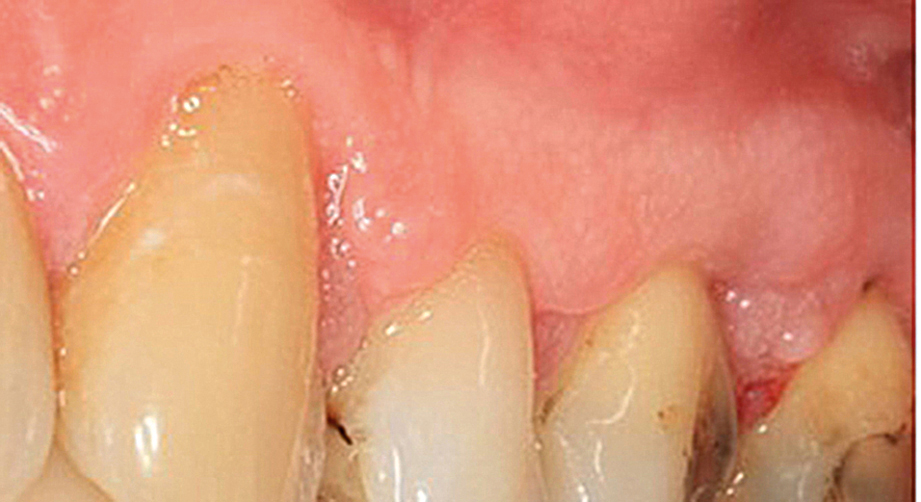

Vid en störd oral homeostas ökar risken för oral candidos, som kan ses som rodnader (Figur 1) eller vita beläggningar. En vanlig orsak till svamptillväxt är mun­torrhet, som i sin tur kan vara åldersrelaterad och/eller läkemedelsinducerad. En rubbad balans i munhålans mikroflora kan även uppkomma vid antibiotikaanvändning, cytostatikabehandling och behandling med inhalationssteroider. Vid inhalationsbehandling med steroider är det viktigt att inte bara uppmana till sköljning med vatten efter inhalation, utan även säkerställa att patienten använder sin inhalator korrekt och tillräckligt vinklad, för att minska deponeringen av läkemedel i munnen. Candidos kan behandlas inom både tandvården och sjukvården, beroende på vart patienten vänder sig.

Figur 1.